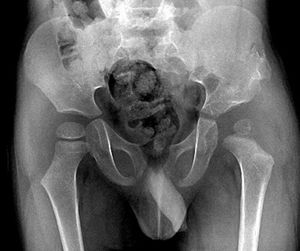

髖關節脫位--X片1.有明顯外傷史。

2.患髖腫、痛,活動受限。

3.患髖屈曲內收、內鏇畸形,或外展外鏇畸形。

4.X線拍片:可見脫位,或合併髖臼骨折。